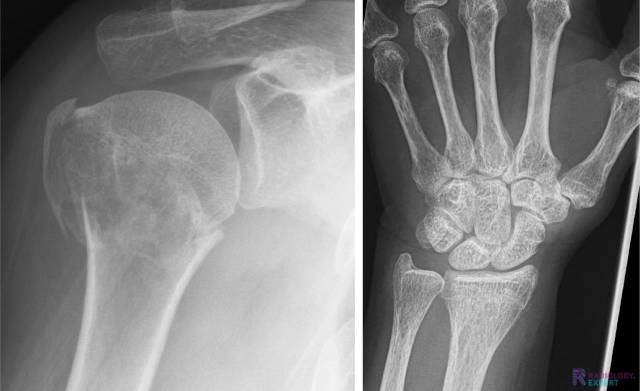

Figuur 1. Laterale en anterior-posterior opname van de linker onderarm/pols. Een kind (9 jaar oud) met distale radiusschacht & ulnaschacht fractuur. Beide tonen een dorso-ulnaire dislocatie over circa een schachtbreedte.